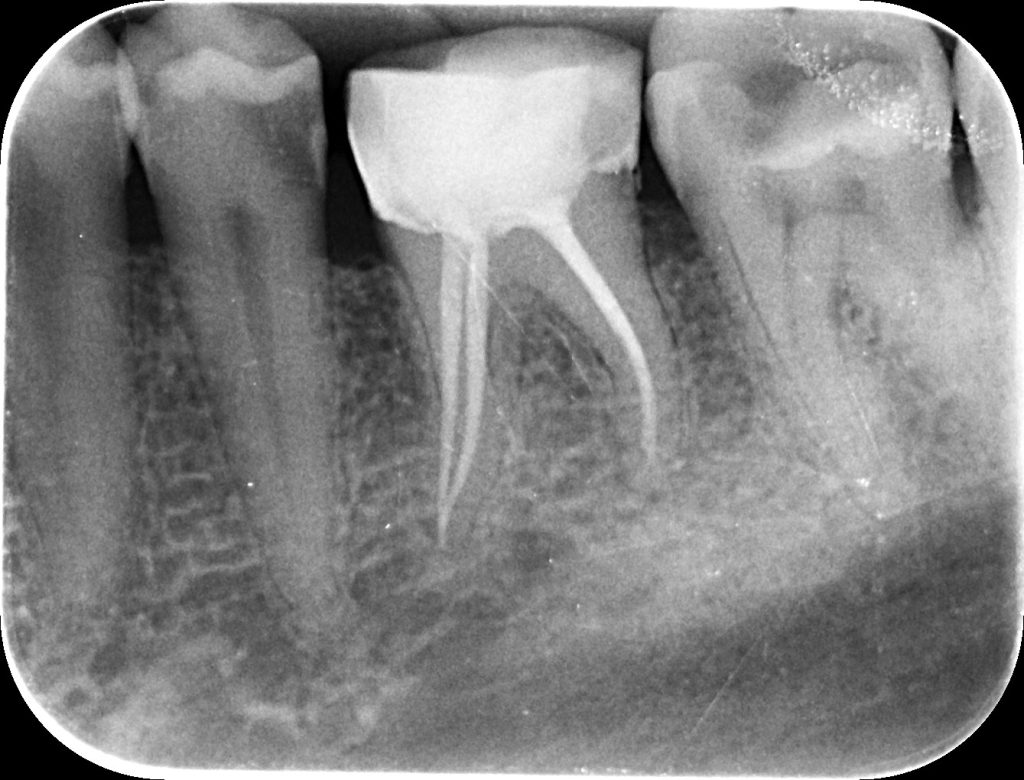

• Obturarea canalelor radiculare – acestea sunt sigilate etanș cu materiale biocompatibile, prevenindu-se astfel reinfectarea.

Restaurarea dintelui după tratamentul endodontic

Având în vedere pierderea semnificativă de țesut dentar dur, dintele tratat endodontic necesită adesea reconstrucție cu pivot din fibră de sticlă și protezare prin coroană dentară, pentru a-i reda rezistența mecanică și a preveni fracturarea.